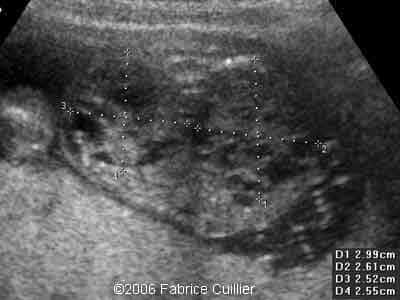

2D transverse view at 19 weeks

4B

2D parasagittal view at 19 weeks

5